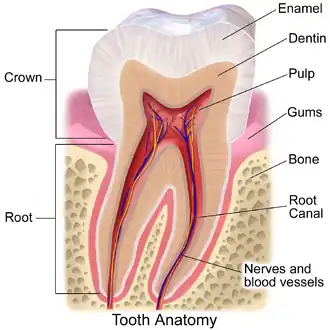

In dentistry, the crown is the visible part of the tooth above the gingival margin and is an essential component of dental anatomy. Covered by enamel, the crown plays a crucial role in cutting, tearing, and grinding food. Its shape and structure vary depending on the type and function of the tooth (incisors, canines, premolars, or molars), and differ between primary dentition and permanent dentition. The crown also contributes to facial aesthetics, speech, and oral health.

The anatomical crown refers to the portion of a tooth covered by enamel, it includes three main layers: enamel, dentine, and the pulp chamber.[3]

The pulp chamber is the innermost part of the anatomical crown and contains blood vessels, nerves, lymphatics, and odontoblasts.[3] It plays a role in dentine formation, nutrient delivery, and pain response.